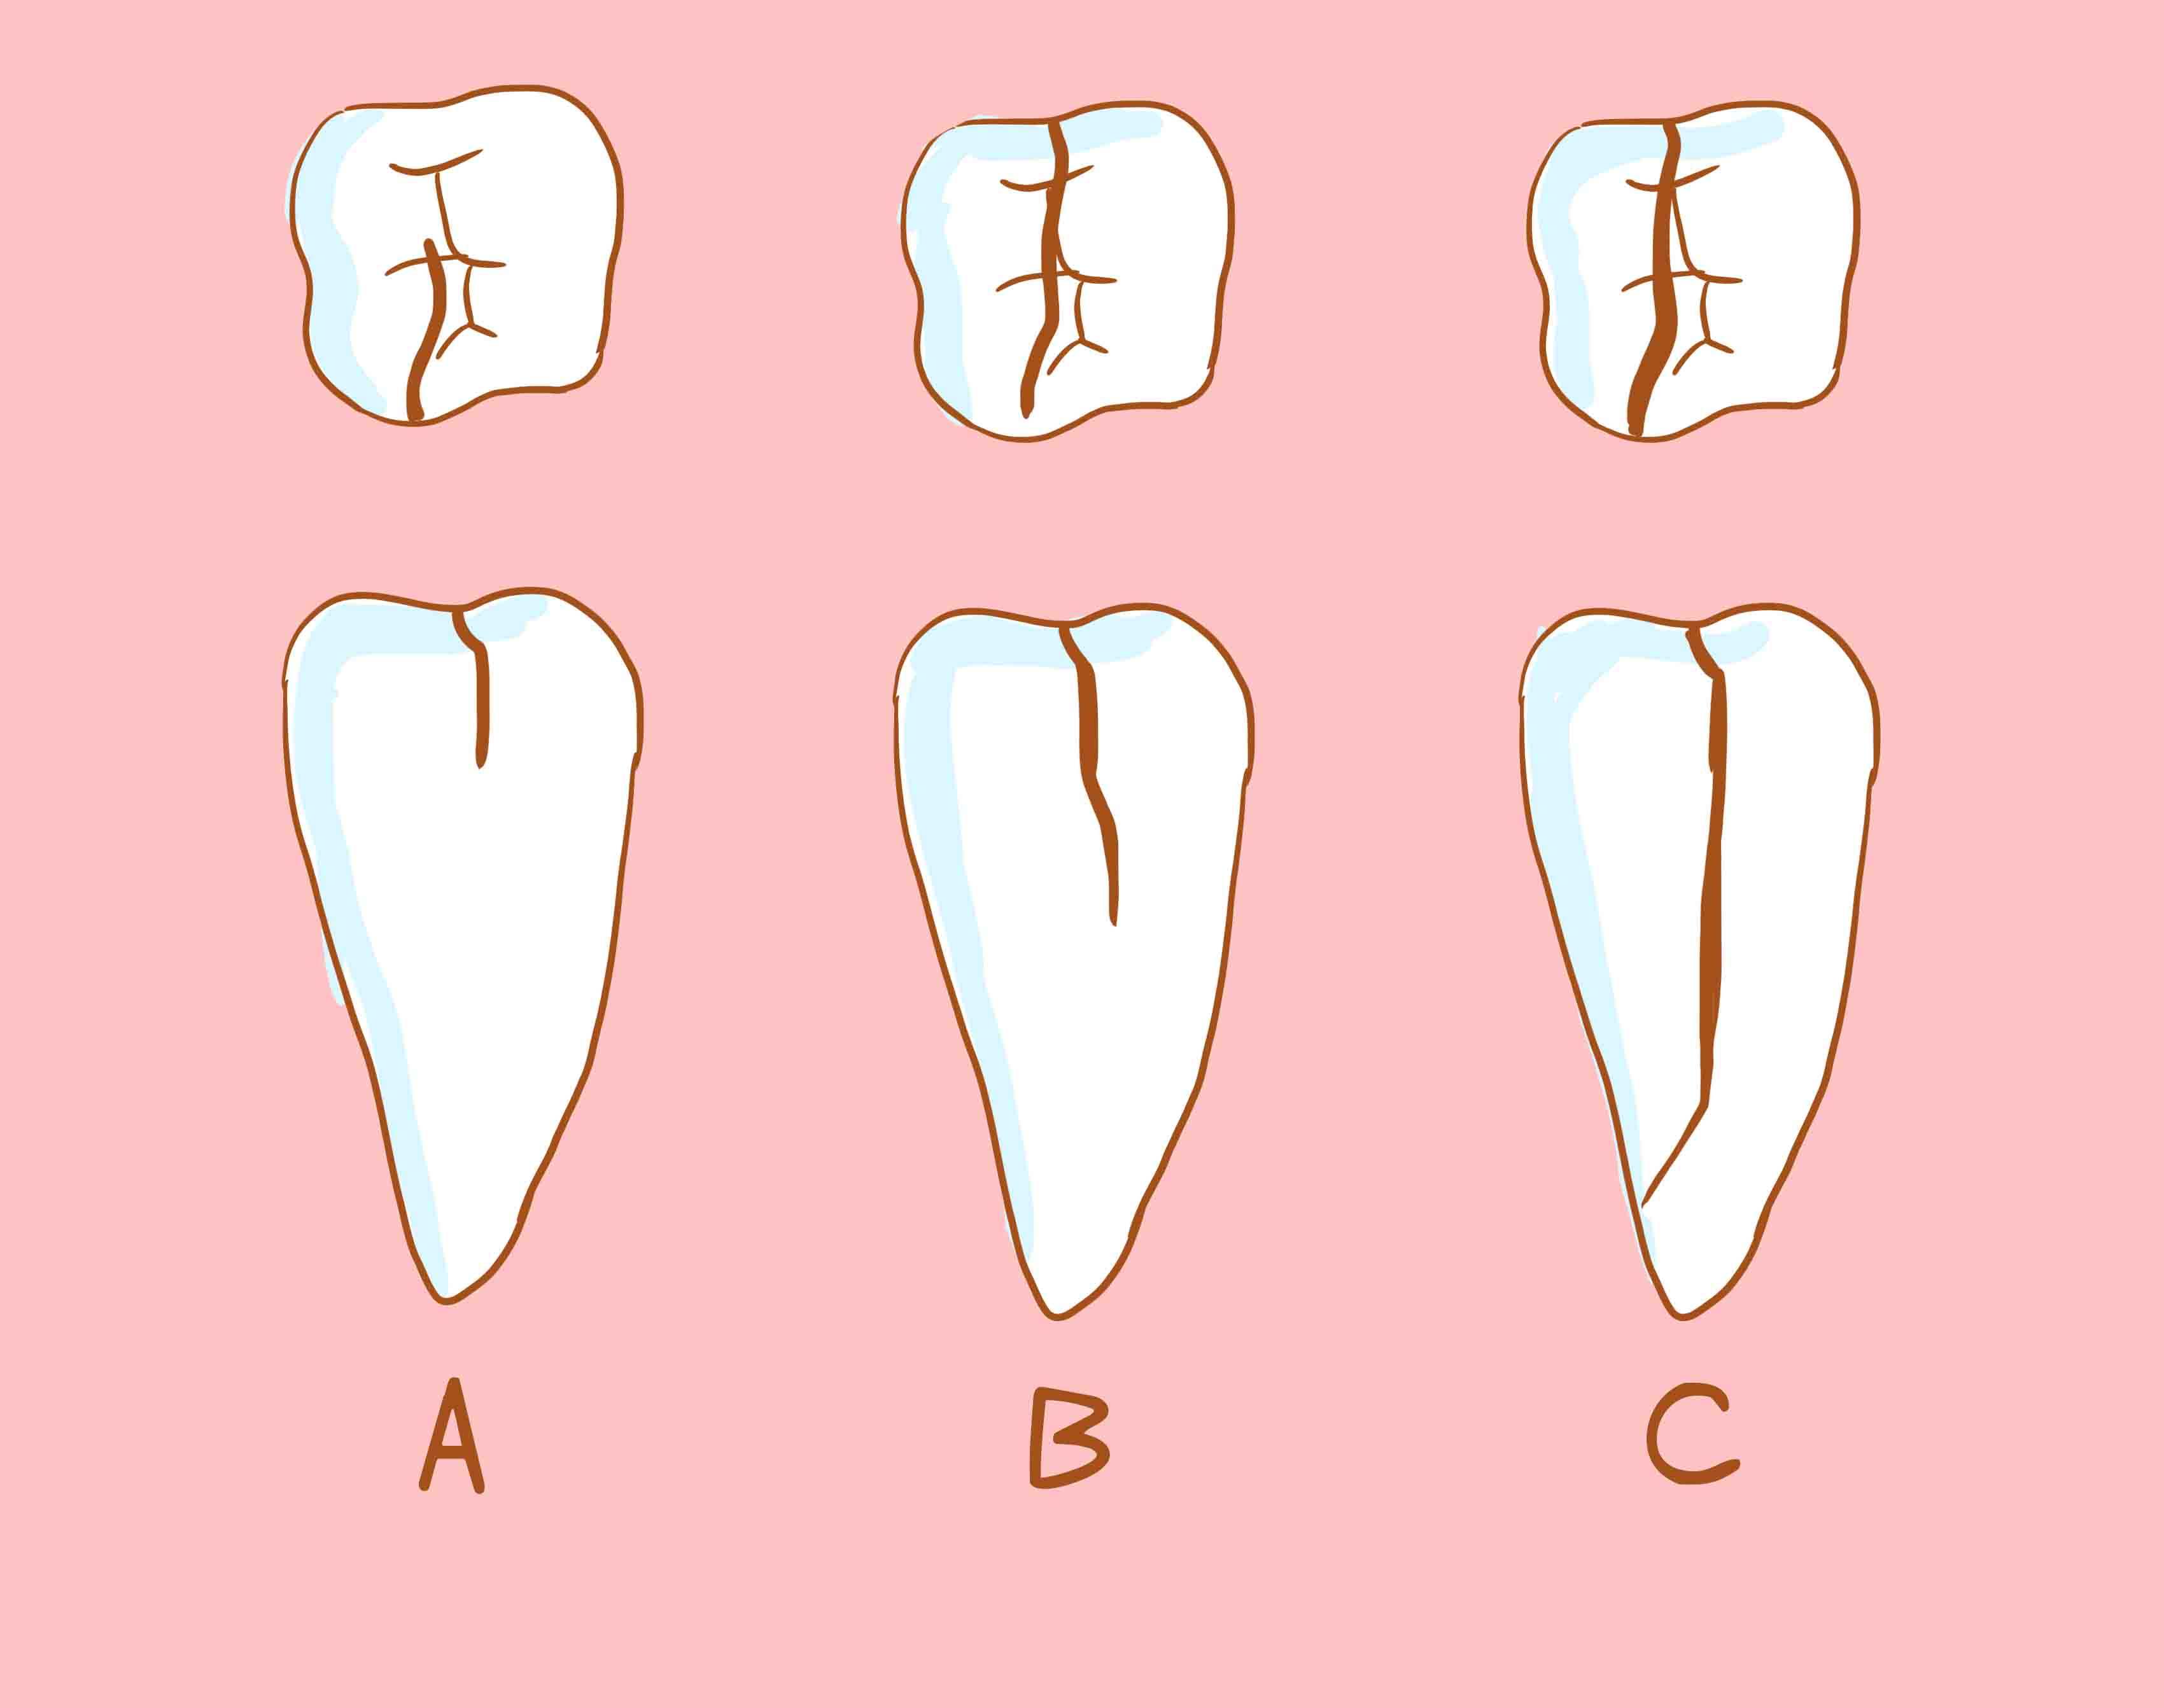

牙隐裂

- 牙隐裂,又称微裂,一般是指牙齿表面有特别微细的不易被发现的异常裂纹,由浅至深可以到达牙髓,最后导致牙齿的劈裂。患者常伴有牙本质过敏症状,长期的咬物疼痛,甚至可以呈撕裂样牙痛。多发生于上颌磨牙,其次是下颌磨牙和上颌前磨牙。

- 牙隐裂的治疗措施因病变程度而异,可选择调和、充填、冠保护、根管治疗等措施。

- 预防要点:

①不要用牙齿咬过硬的食物如蚕豆等。

②嚼骨头之类较硬的食物时,用力宜小,速度宜缓。

③定期进行口腔检查,如发现存在过锐、过陡的牙尖可适度调磨消除。

④重度深覆合、牙齿重皮任耗,特别是有夜磨牙表现的患者,最好夜间戴用咬合垫。